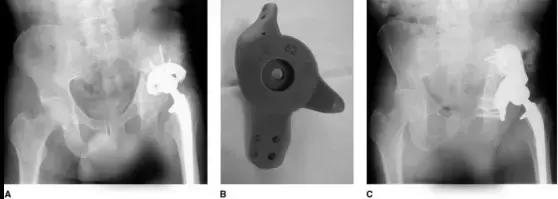

三翼臼杯可以通过对髂骨、坐骨打入多向螺钉获得早期稳定,其多孔臼杯允许骨长入,与加强环相比中期生存率有所提高,但其费用较高,术前准备时间较长,术中软组织损伤较大,且缺少远期随访证据(图 8)。

图 8(A)既往做过全髋关节置换术联合骨盆放疗的患者。术前骨盆平片显示髋臼假体上方移位,和可能继发于放疗骨坏死的骨盆不连续(B)定制三翼臼杯的塑料模型,它可以跨越髋臼骨缺损区域,在髂骨和坐骨上螺钉固定(C)翻修术后 9 年骨平片,骨盆不连续愈合